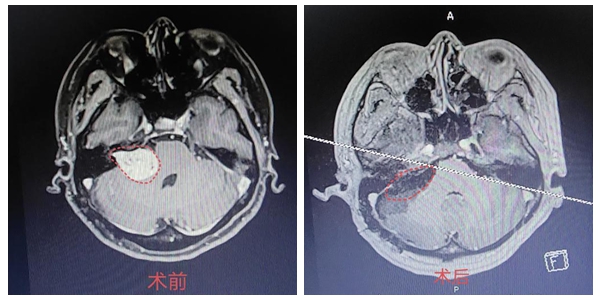

近日,湘雅常德医院神经外科袁贤瑞教授团队为一例三叉神经鞘瘤患者实施行开颅颅底肿瘤切除术,切除了长达13年之久的三叉神经鞘瘤,肿瘤长达3厘米。术后患者面颊部麻木、疼痛等症状消失,目前恢复良好...